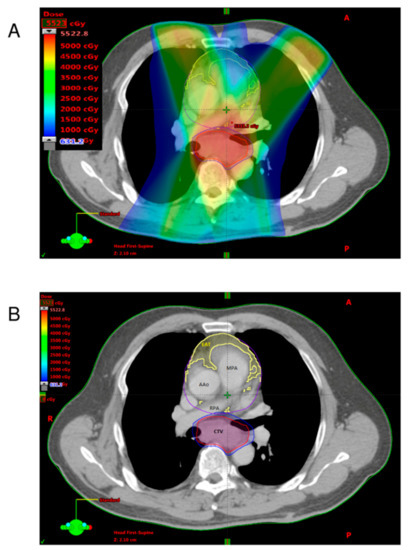

1. Introduction

2. Materials and Methods

2.2. Neoadjuvant Chemoradiotherapy and Surgery

2.3. Quantification of Adipose Tissues

2.4. Definition of EAT-REI